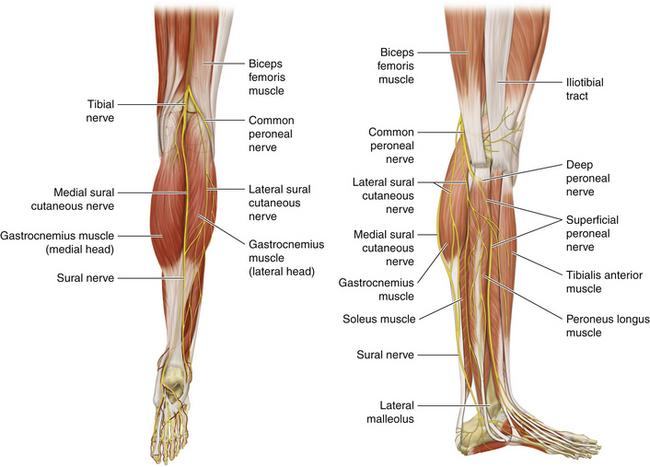

What is the pathway of the tibial nerve?

runs through popliteal fossa

runs with tom dick AN harry though medial malleoulus

bifurcates into medial and lateral plantar nerves

Which muscles are innervated by tibial nerve?

all posterior thigh muscles except short head of biceps femoris (long head, semitendinosis, semimembranosis)

^^technically tibial division of sciatic n

ALL posterior leg muscles (gastrocnemius, soleus, and plantaris. popliteus, tibialis posterior, flexor hallucis longus, flexor digitorum longus)

origin course and distribution of sural nerve

O formed by the union of the cutaneous banches from the tibial and common fibular nerves

C descends between heads of gastroc; becomes superficial at middle of leg; descends with small saphenous vein; passes inferior to lateral malleoulus to lateral side of foot

origin and distribution of tibial nerve

O sciatic nerve

C forms as sciatic nerve bifurcates at apex of popliteal fossa; descends through popliteal fossa; runs inferior to tibialis posterior with posterior tibial vessels; terminates beneath flexor retinaculum by dividing into medial and lateral plantar nerves

D supplies plantar flexor muscles of the posterior compartment of the leg and knee joint

O C D of common fibular nerve

O sciatic nerve

C forms as sciatic nerve bifurcates at apex of popliteal fossa. follows medial border of biceps femoris with its tendon. passes over posterior aspect of head of fibula then winds around neck of fibula deep into fibularis longus where it divides into deep and superficial fibular nerves

D knee joint via articular branch and lateral aspect of posterior leg via sural cutaneous nerve

(common fibular branch of sciatic nerve innervates short head of biceps femoris)